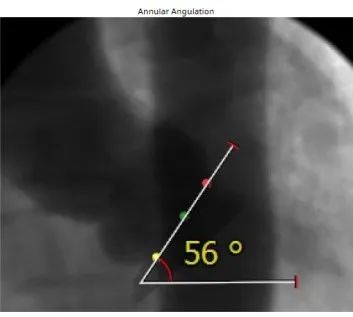

患者资料:84岁女性,既往有高血压、糖尿病、冠心病病史,5年前曾行PCI手术,此次入院诊断为主动脉瓣重度狭窄伴关闭不全,瓣环内径18.5mm,AV Vmax 3.79m/s,LVOT 23.7mm,有效瓣口面积0.6m²。

考虑到患者高龄,合并多种病症,且为PCI后再行TAVR,手术存在较高的血管并发症风险,对TAVR瓣膜器械的选择提出了较高要求。经多专家、多学科讨论,罗建方、谭冠昶教授最终选择使用Evolut PRO+开展此台TAVR手术,以为患者提供最佳的手术体验和更好的手术保障。

手术过程中,罗建方教授发挥经验优势,与谭冠昶、李捷、苏泽宇和徐城烽教授等组成的大湾区术者团队默契配合,穿刺、过弓、跨瓣等一系列操作过程一气呵成,顺利为患者植入Evolut PRO+。